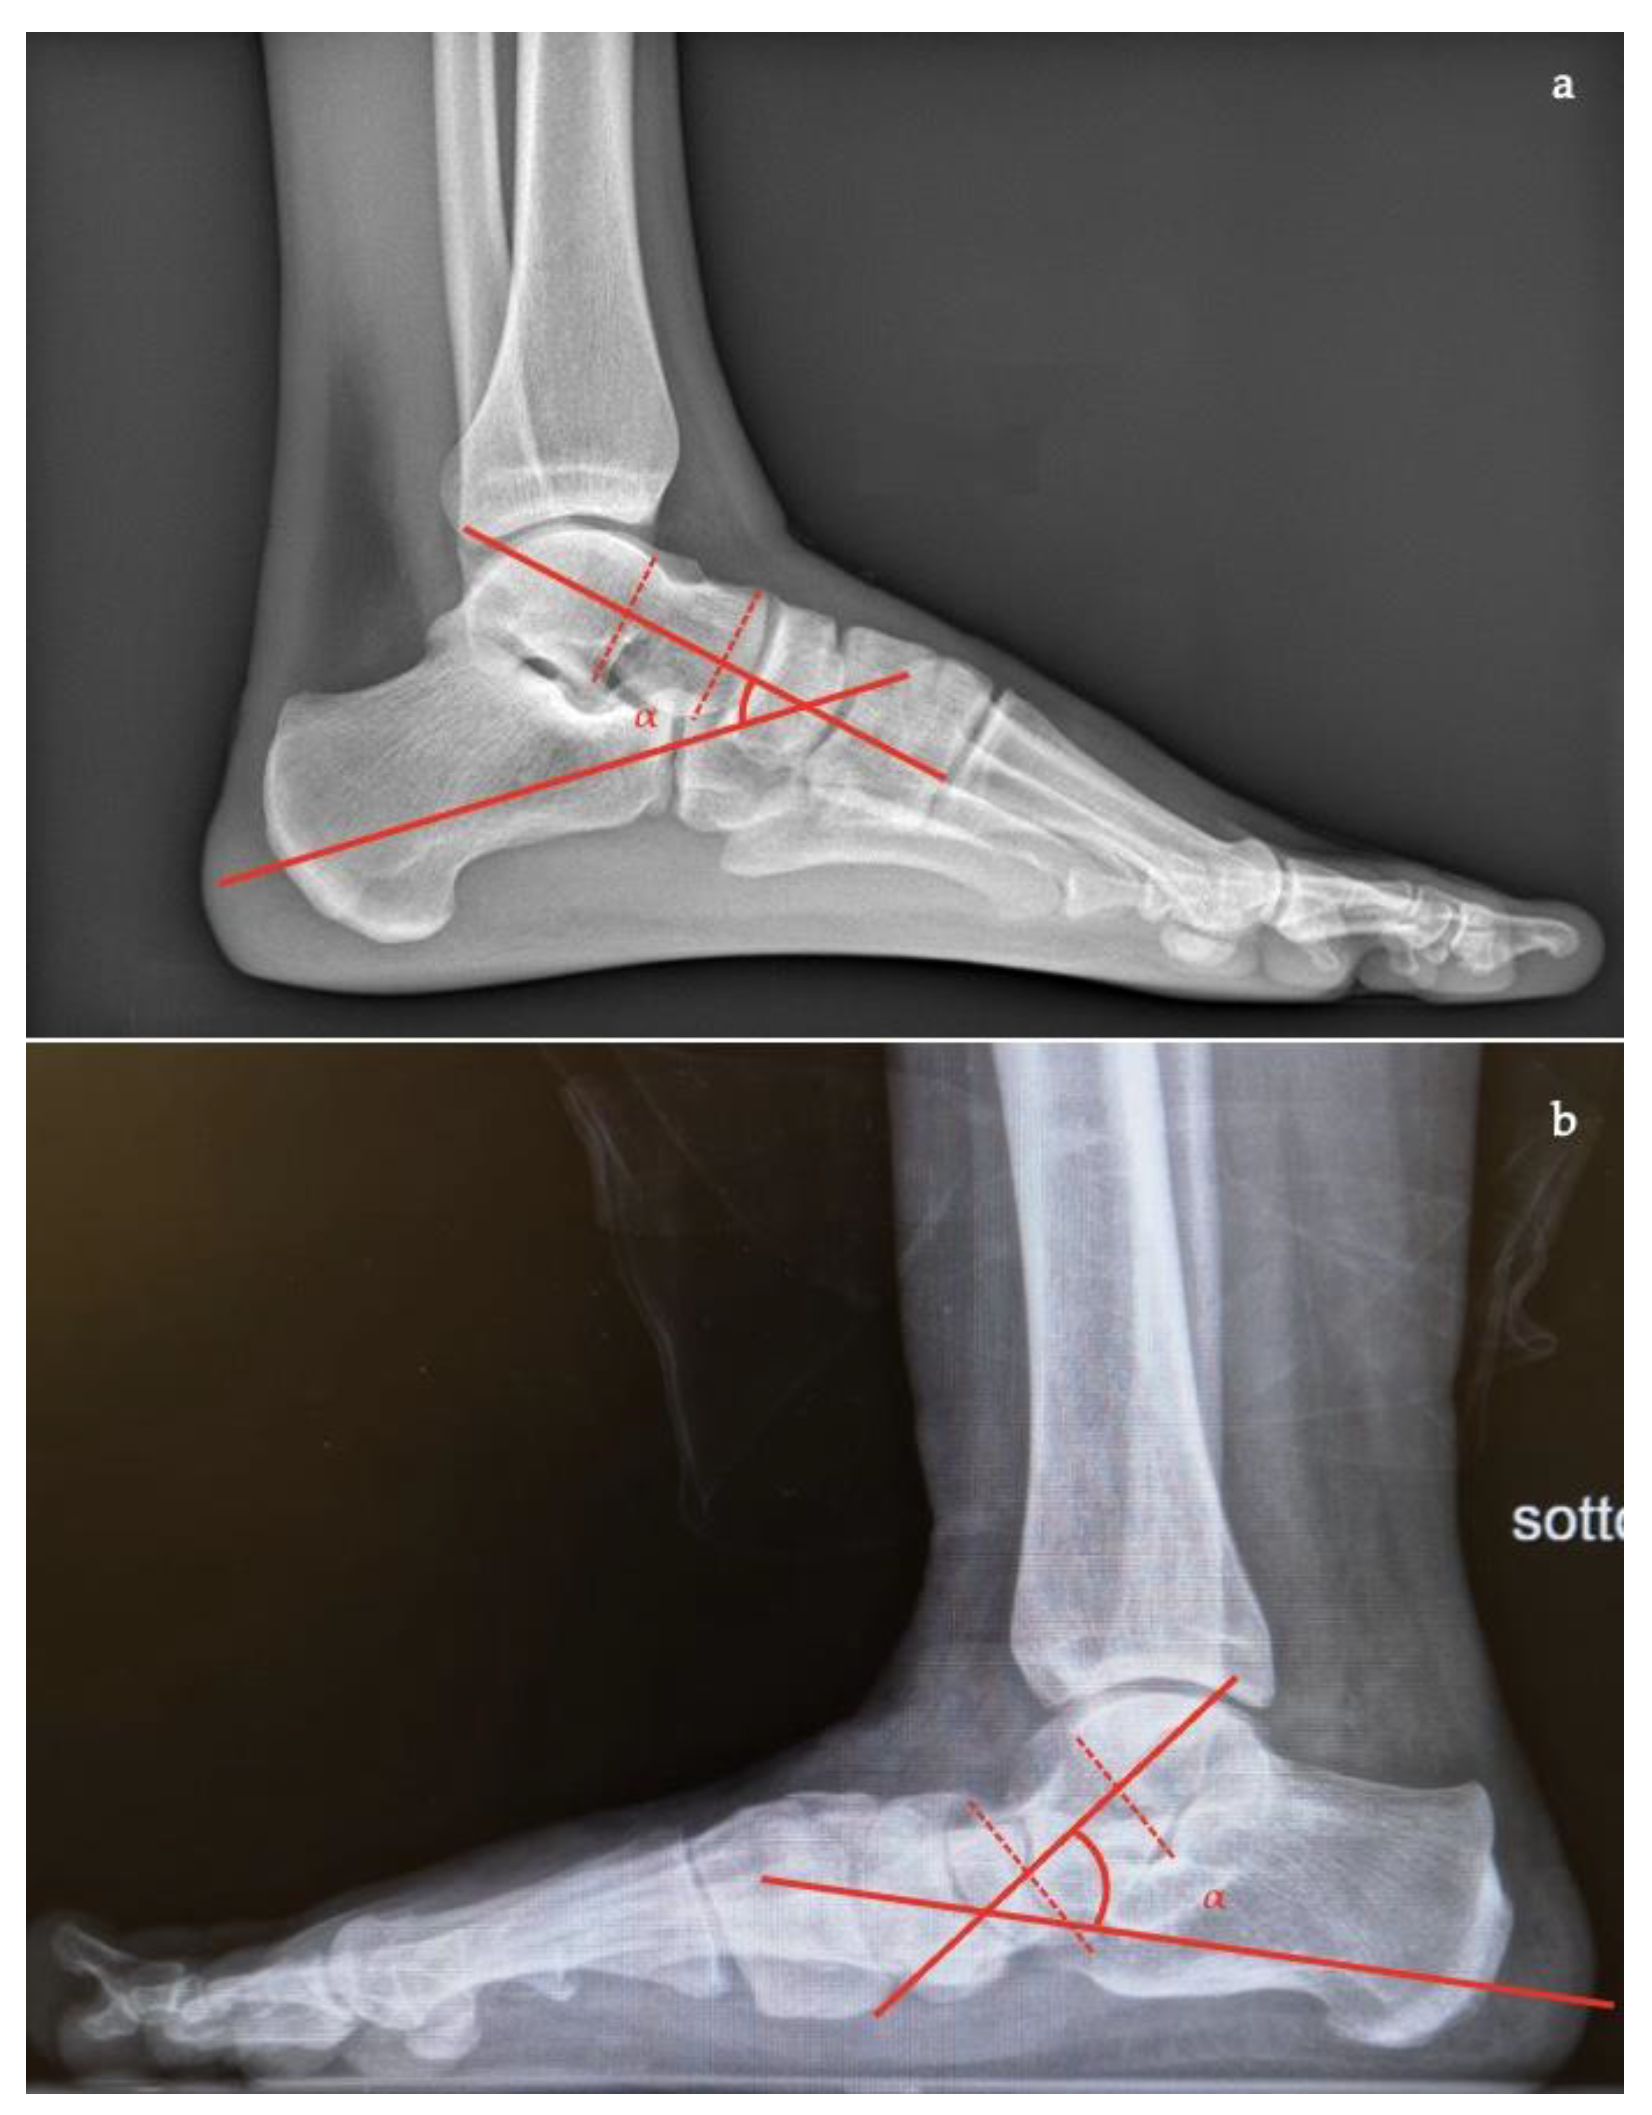

- Talocalcaneal angle is formed by the long axis of the rearfoot and the midtalar line. This angle is increased in pronated feet on both the AP and lateral views (normal <45°, flatfoot >45°) (Figure 7);